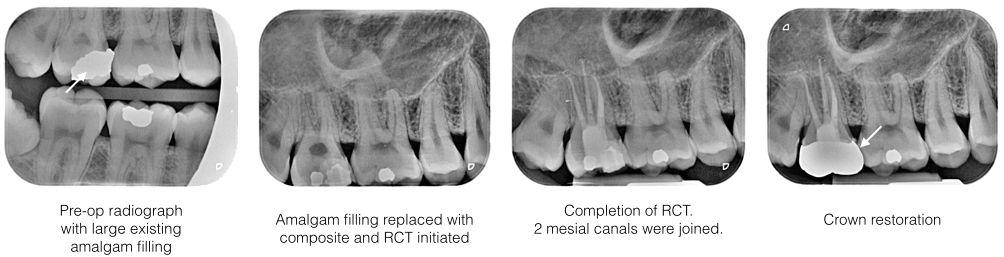

Examination : Tooth 17 has a large old amalgam restoration. Bite test was positive whereby pain was noted upon releasing of bitting pressure. Cold test is positive suggesting the tooth is still vital. There was a hairline crack noted under microscope upon removing of old amalgam filling

Diagnosis : Acute apical periodontirs 17 due to crack tooth.

Treatment : Old amalgam restoration was replaced with composite filling and RCT was carried out under rubber dam isolation. Under microscope, all 4 root canals (MB1, MB2, DB, P canals) were located shaped, cleaned and obturated up to full working length. The tooth was subsequently restored with a semi precious metal crown.